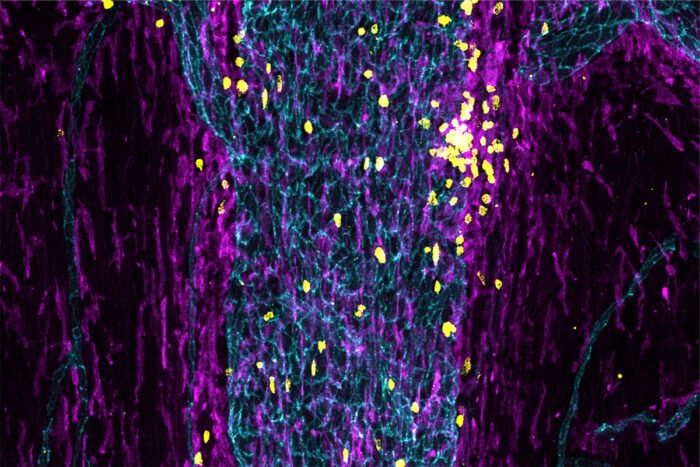

Cellule immunitarie (gialle e viola) riempiono un seno (giada) nello strato esterno delle meningi, il tessuto che circonda il cervello e il midollo spinale. I ricercatori della Washington University hanno scoperto che le cellule immunitarie di stanza in tali seni monitorano il cervello e attivano una risposta immunitaria se rilevano un problema.

Gli esperimenti hanno dimostrato che i seni durali erano pieni di molecole dal cervello e di cellule immunitarie che erano state trasportate con il sangue. Erano rappresentati diversi tipi di cellule immunitarie, comprese alcune che raccolgono e mostrano molecole sospette dal sangue e altre che sondano le molecole sospette e vi rispondono montando una difesa.